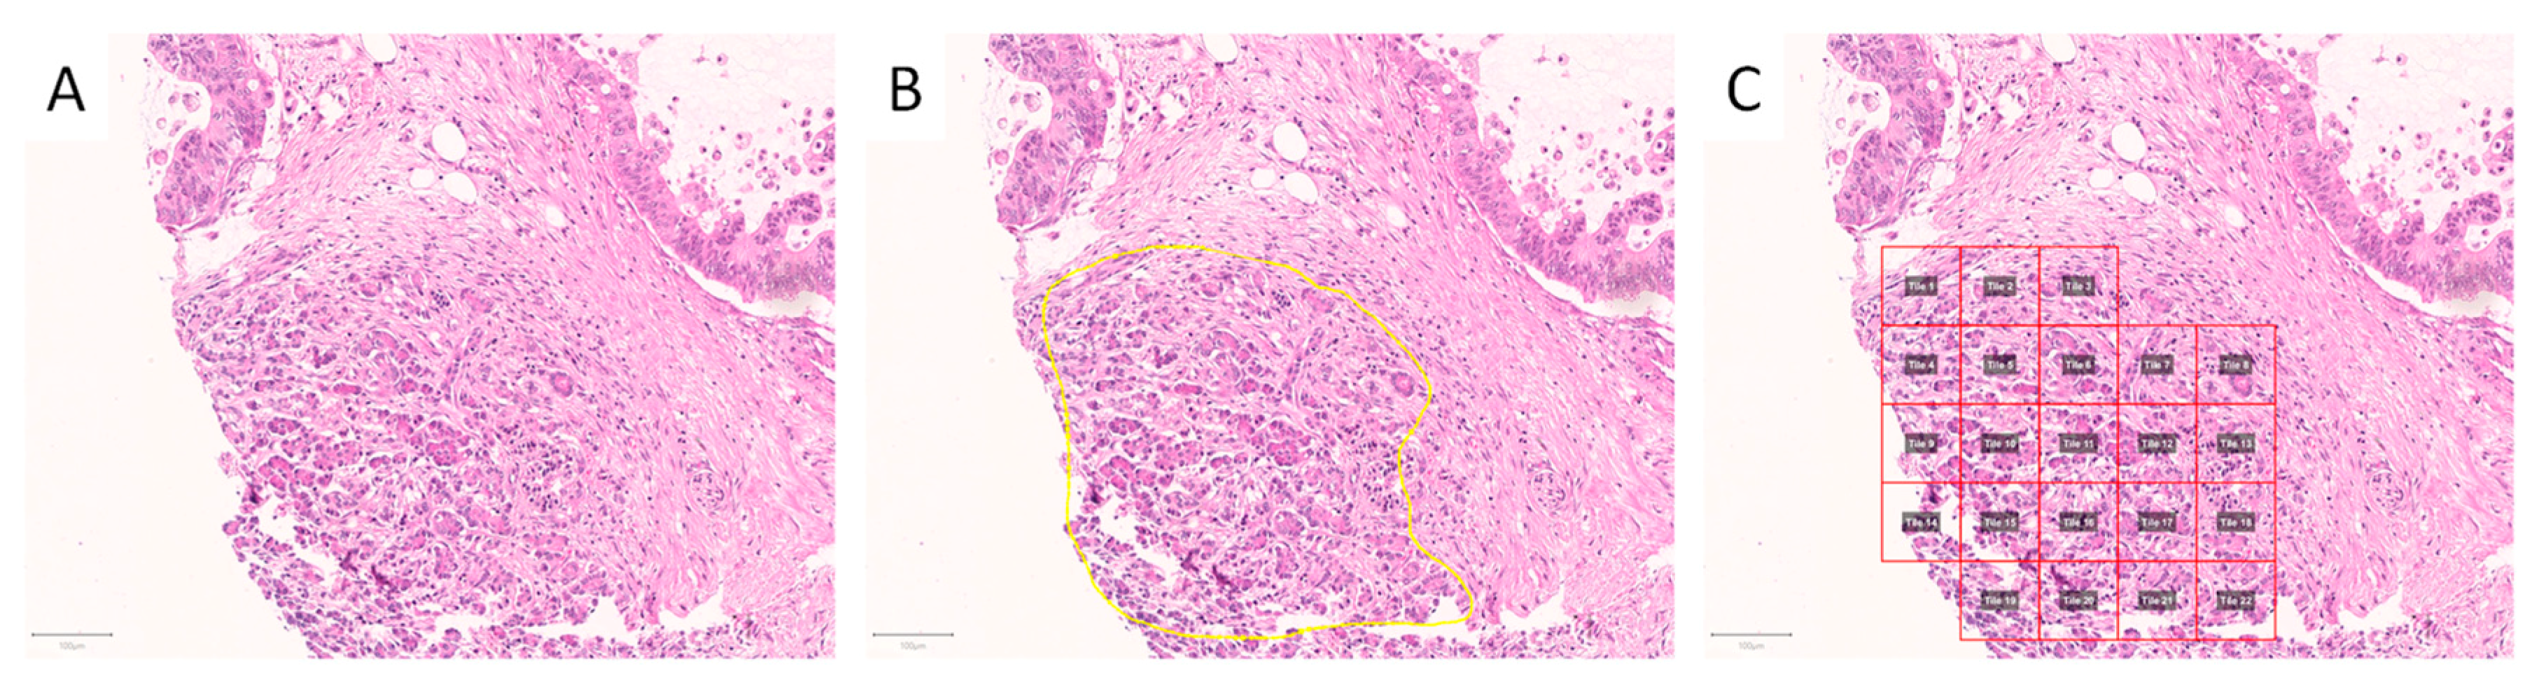

2.2. Image Patch Extraction

4.2. Annotation of Regions of Interest and Image Patch Extraction